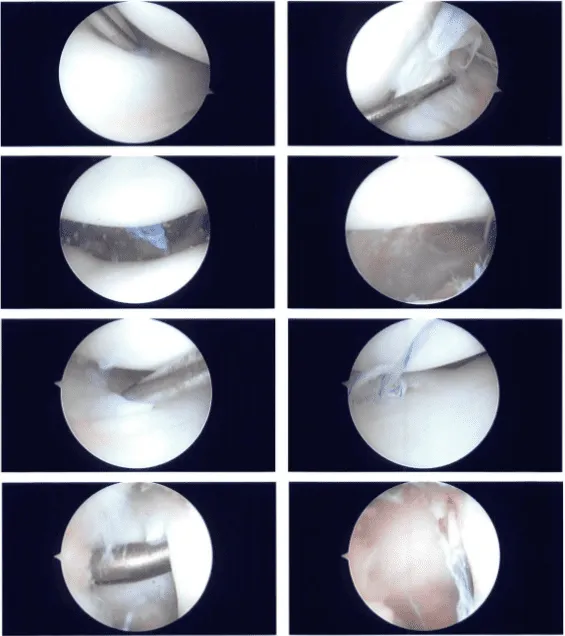

An arthroscope was introduced through a lateral entrance hole. The spinal needle was used to create the medial entrance portal. The medial meniscus was examined and found to have a peripheral tear along the body of the meniscus.

There was no injury to the cartilage. The ACL was found to be intact when the intercondylar notch was examined. Fraying of the posterior horn of the lateral meniscus was discovered during an examination of the lateral tibiofemoral compartment.

The cartilage was not damaged. The patellofemoral compartment was found to have complete cartilage. It was chosen to repair the medial meniscus tear. The tear was prepped with a rasp and shaver, and a FasT-Fix and arthroscopy were introduced through the lateral portal and the medial portal, respectively.

A horizontal mattress suture was placed and then cut. Fixation was successful. Photographs were taken and preserved. The lateral meniscus posterior horn was also shaved, and photographs were taken and stored.

Chondroplasty picks were used, as well as four microfractures, to allow bone marrow venting. Fat globules, followed by blood, could be observed venting out of the holes to help the meniscus mend faster. The final photographs were shot and preserved. The knee had been completely irrigated and drained.

Intraoperative Images